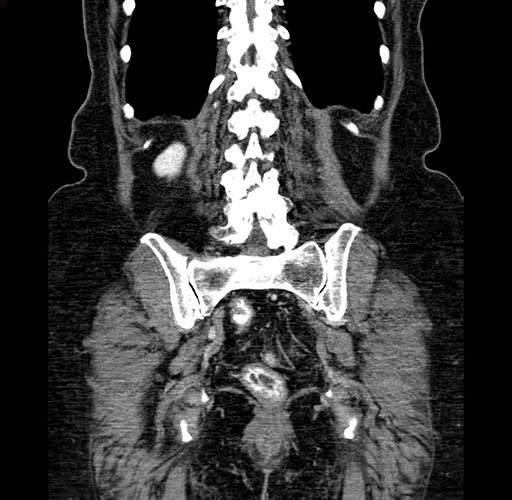

Pre-Chemo: Coronal Venous

Coronal Venous